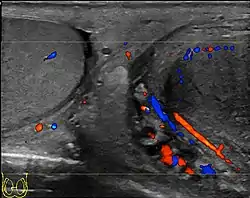

- المسح بالموجات فوق الصوتية